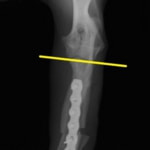

症例:柴犬 3歳

左後肢の完全挙上を主訴に来院されました。触診にて近位足根関節の過伸展を、レントゲン検査にて左足根関節周囲の軟部組織の腫脹、ストレス撮影によって距骨・踵骨と第4足根骨・中心足根骨間の脱臼および過伸展を認めました。

術中において、浅趾屈筋腱を剥離、内方へ牽引し、直接踵骨から第4足根骨までピンを挿入し(あらかじめ細いピンで下穴をあけておくとよい)、テンションバンドワイヤー法を併用し、関節軟骨の掻爬と海綿骨移植を実施しました。

術後レントゲン画像上に癒合が認められるまで約2ヵ月間は、運動を制限する必要があります。

術前正面像